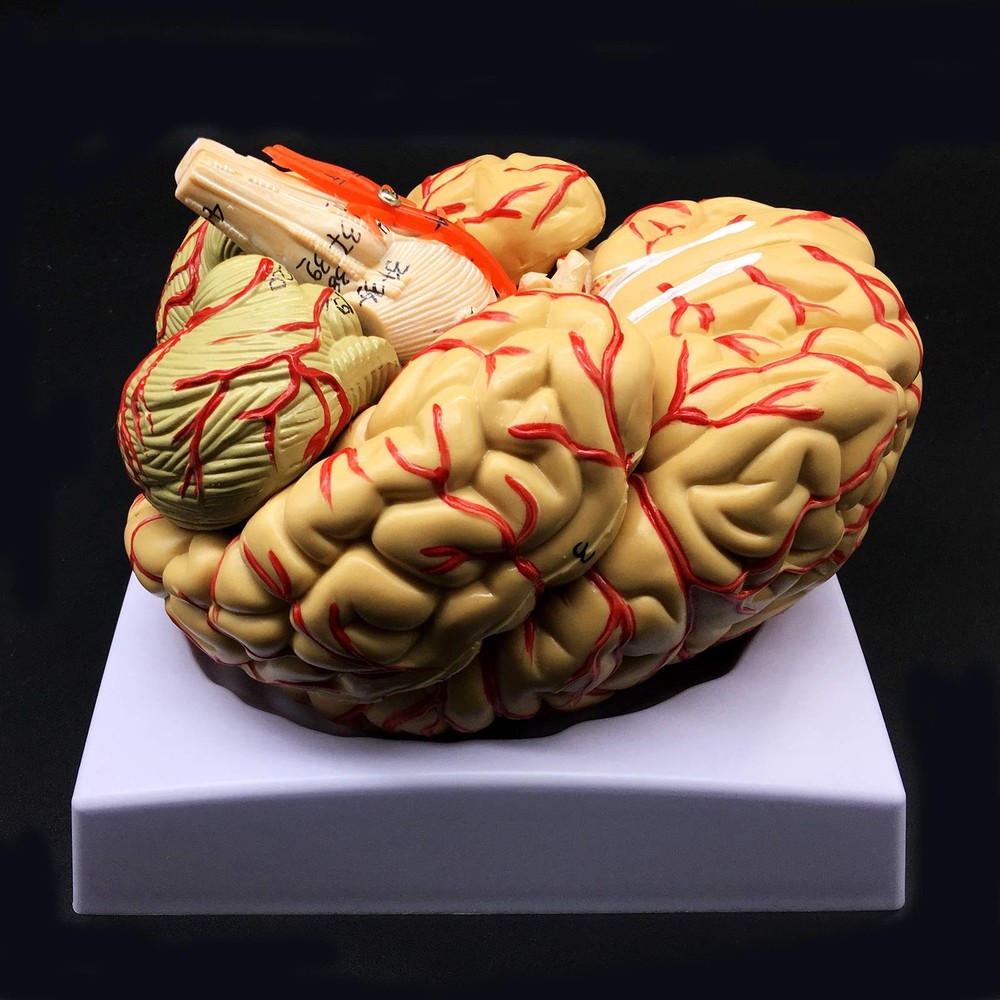

Check the listing for details. Human Brain Model, Anatomically Accurate Brain Model 8-Part Human Brain Anato.... Condition: New. Listed at 66.01 USD. Functional characteristics: the model consists of nine components: sagittal section of brain, cerebral hemisphere, cerebellum and brainstem. Life-size human brain model mounted for use in patient education or anatomical study.